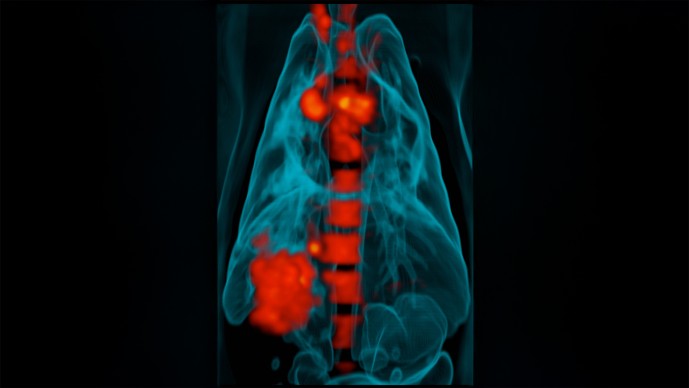

The story goes back more than a decade, to 2005, when a group of researchers led by Dr. Douglas Young won a Grand Challenges in Global Health grant. Working with Dr. JoAnne Flynn, they used the grant to develop a new technique for working with tuberculosis: a combined PET scan and CT scan. Using this new method, they were able to examine Mtb lesions, or granulomas, much more closely than they could using either technology alone. What they discovered, to their surprise, was that LTBI and tuberculosis disease weren't binary - rather than being either active or inactive, Mtb lesions were on something of a spectrum. Some of them were completely asleep. Others were active but not active enough to overcome to the body's immune system. Still others were waging a war - and winning.

This gave Dr. Lin an idea. If she used this new technology to look at what happened during Mtb infection, she might find a difference between an infection that progressed straight to tuberculosis disease and one that stayed latent. So in 2009, with a Grand Challenges Explorations grant to explore latency in tuberculosis, she monitored monkeys who'd been infected with Mtb, and what she found was that there was indeed a difference: In latent infections, lesions stopped growing within several months of infection; after that, they just stayed dormant. Meanwhile, in infections that progressed straight to tuberculosis disease, new lesions kept popping up over time - so many and so quickly that, though latency isn't declared until six months after infection, Dr. Lin found she could tell within just six weeks which monkeys would have which kind of infection.